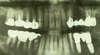

Panorex montrant le projet chirurgical et prothétique